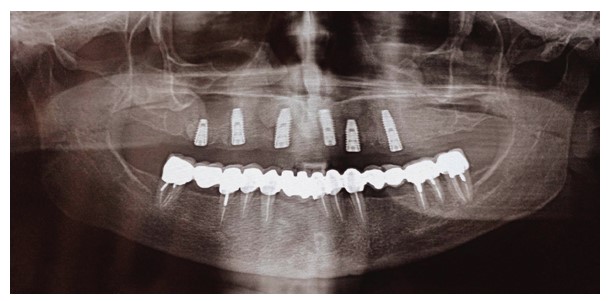

A 62-year-old female patient presented for maxillary rehabilitation with an implant-supported fixed prosthesis. Clinical examination revealed a failing conventional fixed partial denture extending from tooth #14 to #21, exhibiting significant gingival recession and radiographic evidence of periapical pathology. Preoperative cone-beam computed tomography (CBCT) using a Planmeca ProMax 3D unit demonstrated a well-defined radiopaque lesion measuring 1.5 × 1.3 cm adjacent to tooth #16, with a buccal-palatal width of 8.2 mm and bone density measuring 1250 Hounsfield units (Fig. 1).

Preoperative OPG showing a radiopaque lesion on the right posterior maxilla.